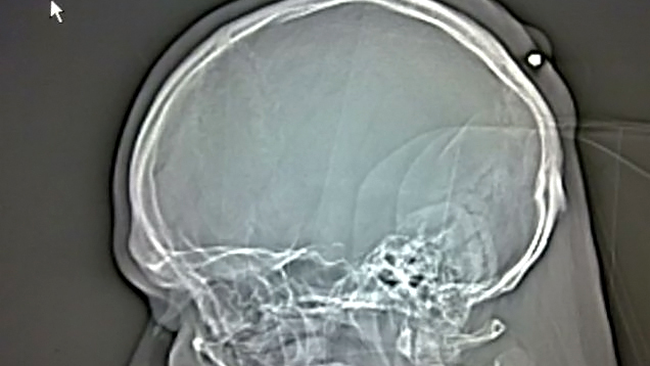

Radiografia barbatului impuscat in

cap